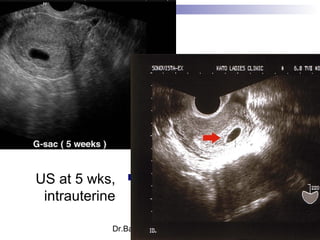

US at 5 wks,

intrauterine

Dr.Basma ,FM,SCU,2012-2013